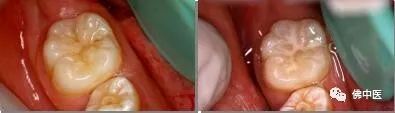

龋齿是不会自愈的,必须由专业的牙科医生进行治疗。没有形成虫洞的初期龋齿,可以用氟化液涂抹清洁龋齿表面,或磨除表层龋坏组织,阻止龋齿继续发展。如虫洞已经很明显,那就要采取填充治疗,即去除患儿的龋坏组织后进行填充,然后塑形抛光(图3)。对于症状比较严重的患儿,则要采取根管治疗。